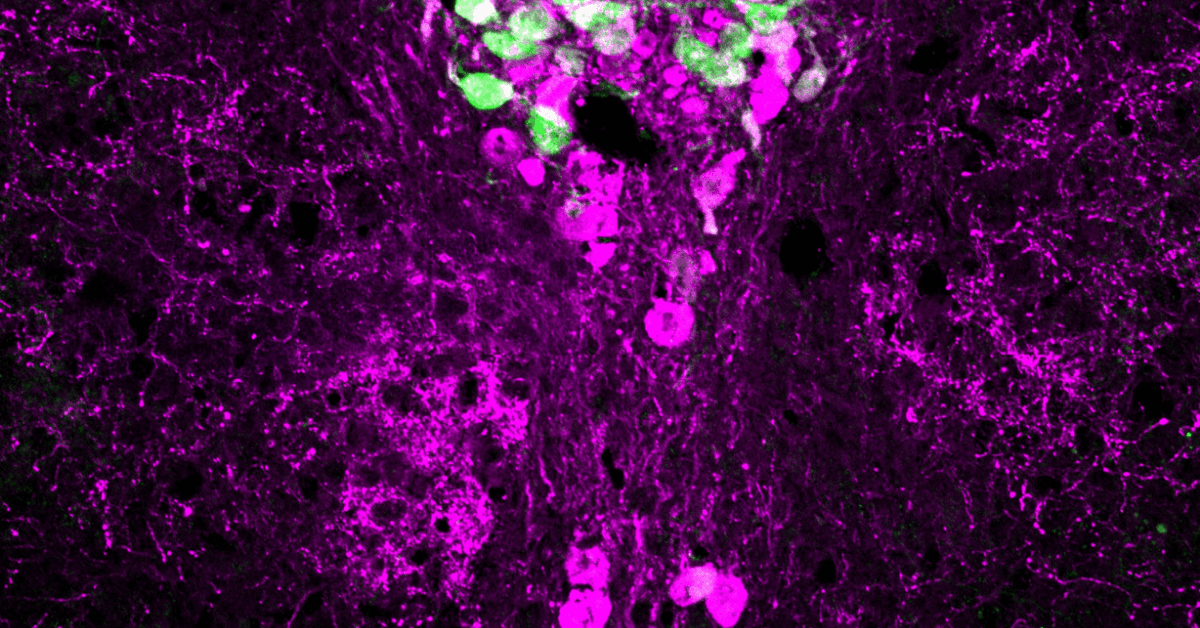

Reversible Morphological Remodeling of Prefrontal and Hippocampal Serotonergic Fibers by Fluoxetine

Serena Nazzi, Marta Picchi, Sara Migliarini, Giacomo Maddaloni, Noemi Barsotti, and Massimo Pasqualetti*

DOI: 10.1021/acschemneuro.3c00837